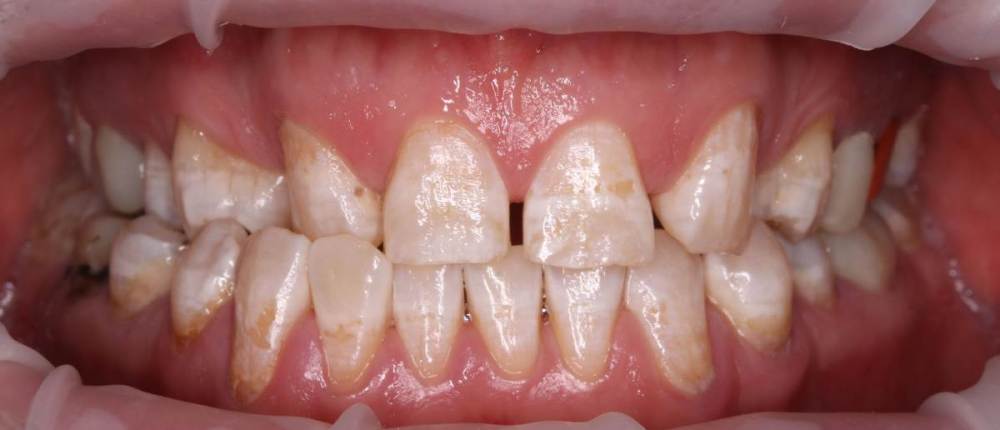

Роман1982 Опубликовано 25 мая, 2021 Поделиться Опубликовано 25 мая, 2021 Добрый день! Очень хотелось бы услышать объективное мнение специалистов. 40 лет На верхней челюсти от рождения не хватает двух резцов (12 и22) Перекрестный прикус В принципе, особо не беспокоит, хотя есть щелчки в суставе слева, если широко открывать челюсть. Из-за неправильно проводимого ранее лечения, встал вопрос об удалении в ближайшее время 25 и 26 зуба сверху и 46 снизу (на фото обведены красным). Ортопед рекомендовал пройти ортодонтическое лечение, т.к. в противном случае в дальнейшем могут возникнуть сложности с имплантами и коронками, может ухудшиться ситуация с суставом. Вот пытаюсь взвесить все за и против. Понимаю, что прикус было бы желательно исправить. Но! При текущем состоянии зубов не навредит ли это им еще больше? Исправление прикуса повлечет за собой необходимость установки на верхней челюсти еще двух дополнительных имплантов (на месте отсутствующих12 и 22). После исправления прикуса велика вероятность тотального протезирования. По словам того же ортопеда, может не хватить высоты сустава и тогда на все зубы понадобиться устанавливать коронки. Стоит ли затевать ортодонтическое лечение в данной ситуации или лучше не трогать то, что как-то функционировало 40 лет? Хотелось бы услышать аргументирование мнение. Ссылка на комментарий

Brigita Опубликовано 1 июня, 2021 Поделиться Опубликовано 1 июня, 2021 я считаю, что ортодонтия Вам показана. Те пятна, которые Вы видите - это определенная форма флюороза, эмаль, конечно страдает. Но, при правильно спланированном лечении и хорошей гигиене, брекеты не ухудшат состояние эмали, но улучшит состояние Вашего организма в целом 1 Ссылка на комментарий